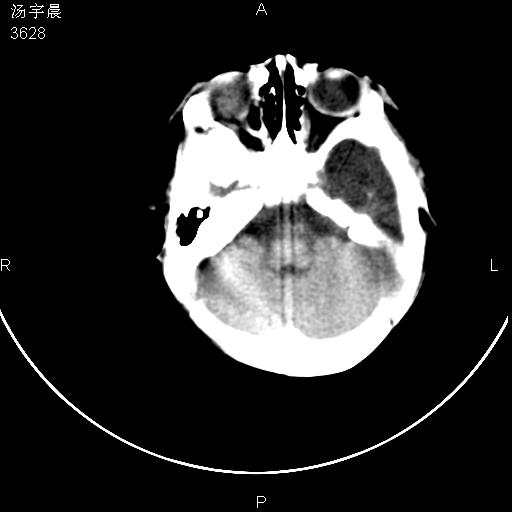

早产儿,现两月大,2月份在某医院诊断病毒性脑炎并治疗,mri报右颞部脑白质片状长t2信号,脑白质模糊。其他不详,现家属要求ct复查 。

双侧大脑半球大片状低密度,无明显占位表现, 符合病毒性脑炎。

小儿病毒性脑炎ct表现缺乏特异性,但其定位分布有一定特异性,单纯疱疹病毒性脑炎ct表现以颢叶病变为主,同时可累及其他脑区或伴出血,乙型脑炎表现为基底及丘脑的病变,流行性腮腺病毒性脑炎则ct表现可正常,故ct检查对病毒性脑炎的定性有重要的价值。 本例支持:病毒性脑炎的后遗改变!